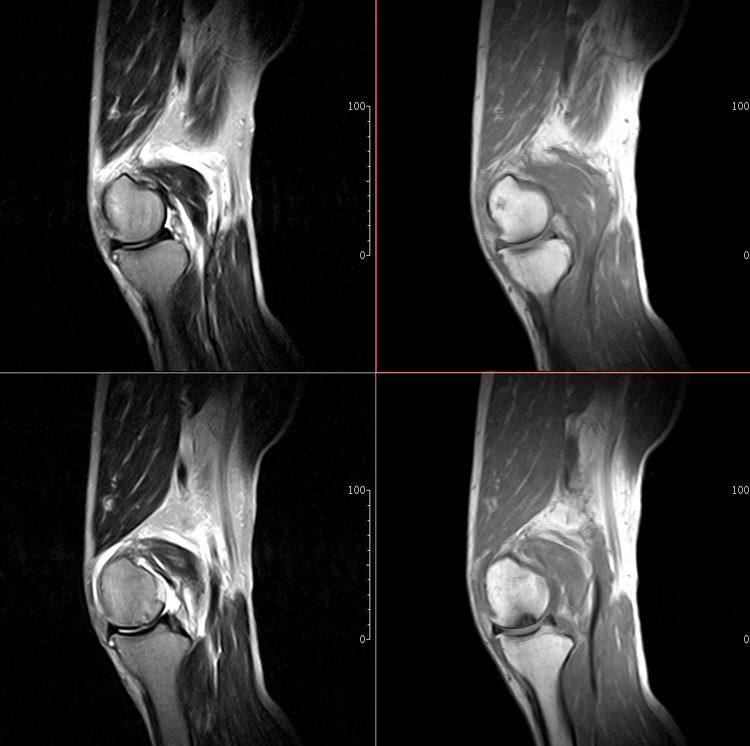

标题: MRI1910:M 687Y。近日因外伤疼痛,而就诊。

m 687y。近日因外伤疼痛,而就诊。有外侧副韧带损伤吗??因片子较差各位请包涵。

这算什么位置呢?矢状位?冠状位?

关节退行性变伴股骨外髁关节面下囊肿,不除外剥脱性骨软骨炎.关节积液,髌骨软化症

体位不标准。关节退变伴关节积液。

1)膝关节骨质退行性改变。

2)由于体位的关系不能确定有外侧副韧带的损伤。

关节退变伴关节积液,外侧副韧带的损伤

关节积液,外侧副韧带的损伤